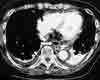

Figure 1

Two days later, the patient againcomplained of epigastric pain and experiencedatrial fibrillation. Becauseof her recent airplane trip, a spiralCT scan of the thorax was obtained toassess for pulmonary embolism. Thestudy demonstrated mediastinal airposterior to the esophagus (Figure 1)and a possible distal esophageal perforation,which was confirmed by ameglumine diatrizoate esophagramthat revealed extravasation of the contrastconfined to the mediastinum(Figure 2).